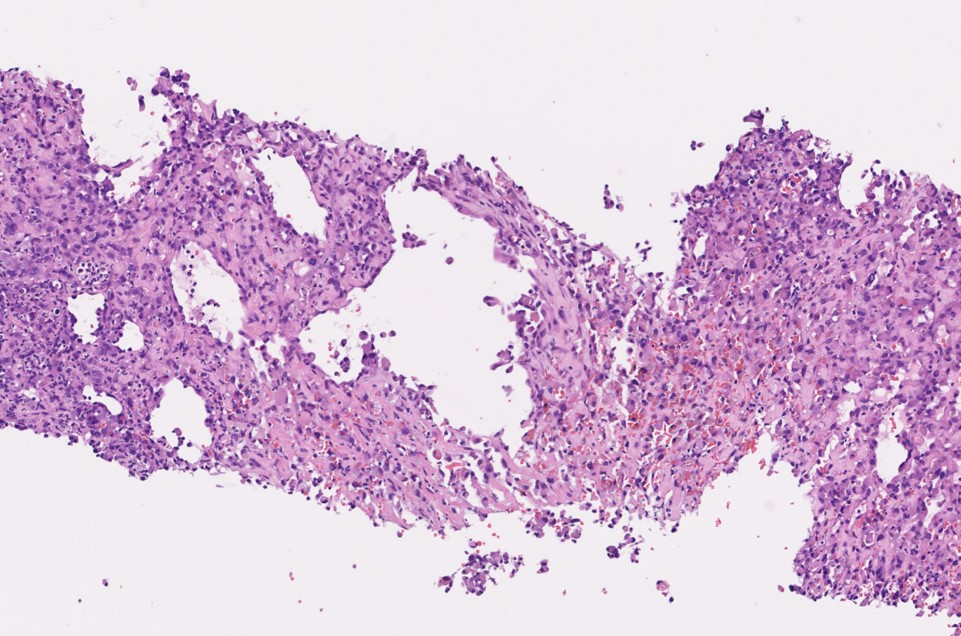

• 病理診断;多くは類上皮血管肉腫

特発性大動脈肉腫における頻度と異なる

• Intimal type:血管内腔に突出する疣贅様の腫瘤

• 血栓と紛らわしい

• 不均一な造影効果を有する

• Mural type:血管の外側に存在する結節状・三日月状の腫瘤

• 血管新生による造影効果